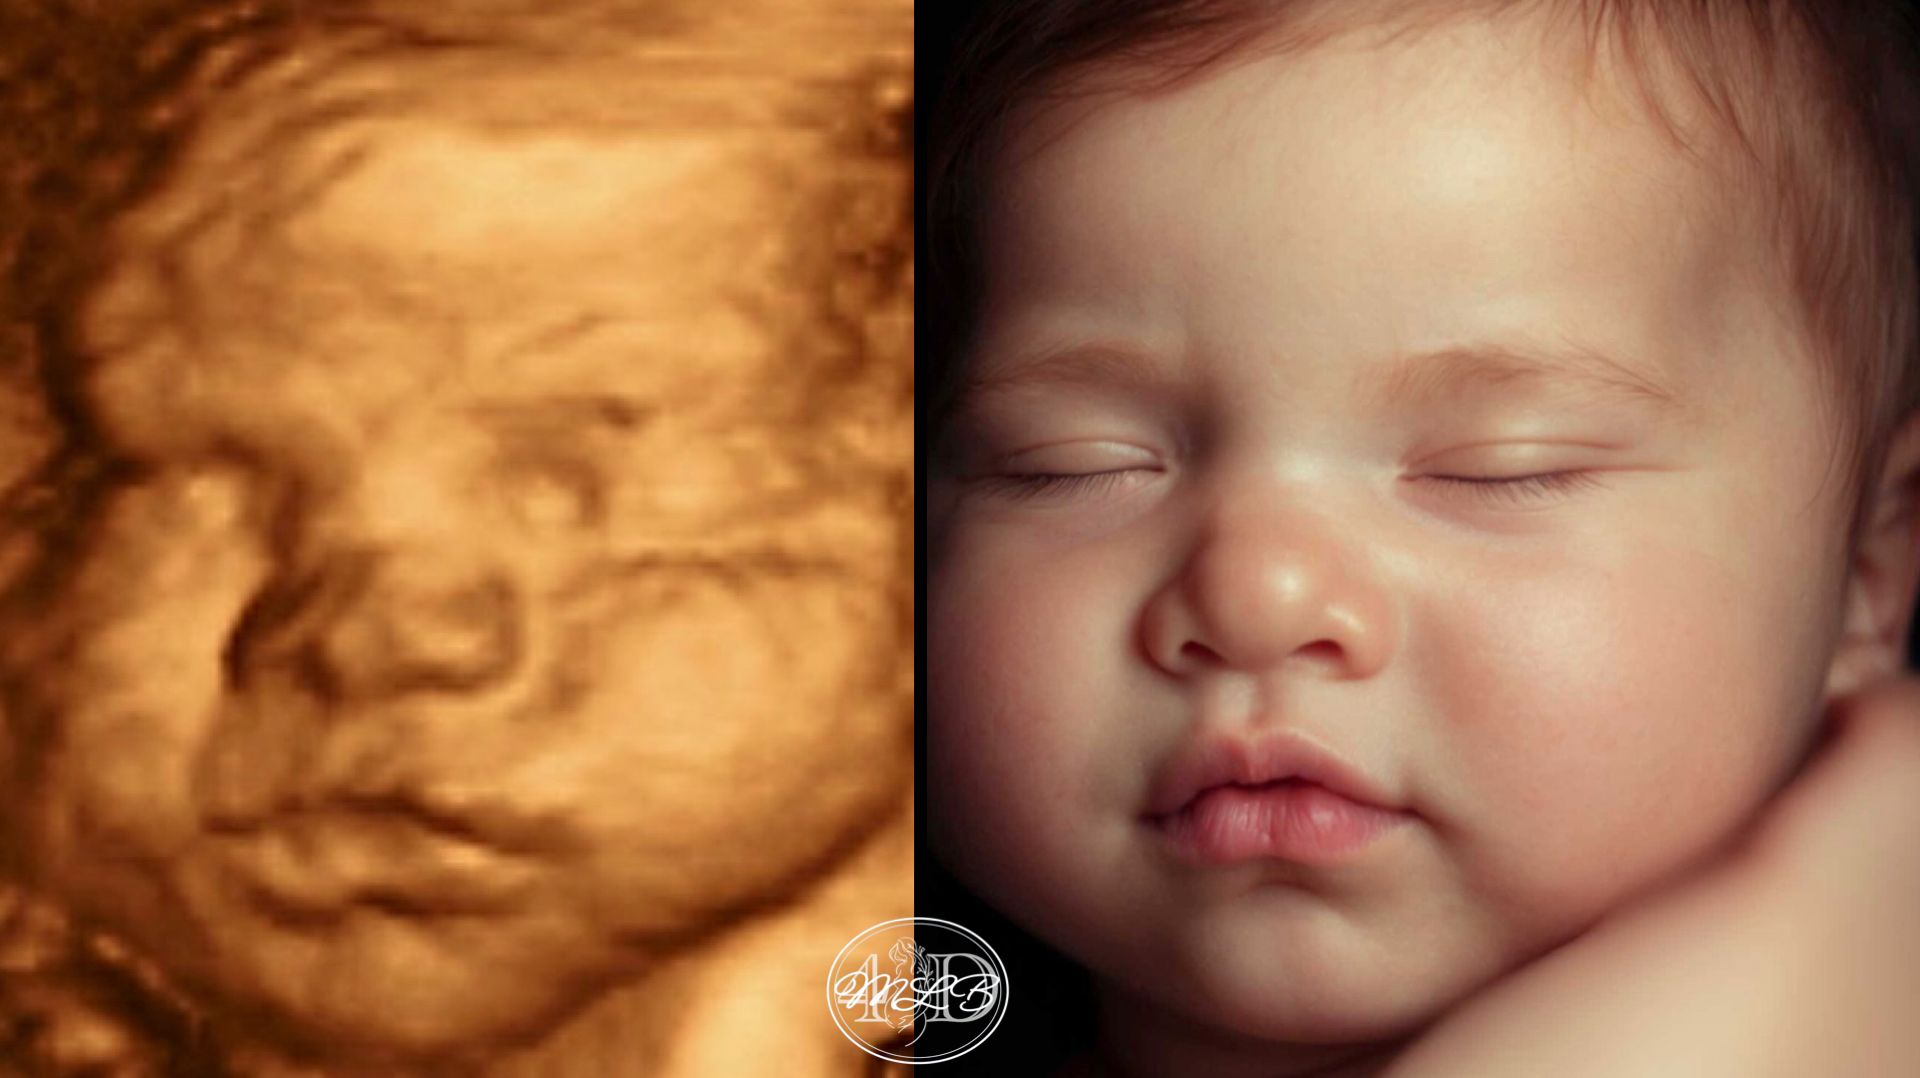

Most Realistic & lifelike photo you can get until the arrival of your little one. Using the newest technology to change your 3d/4d photo into something more realistic without changing any of your baby's features.